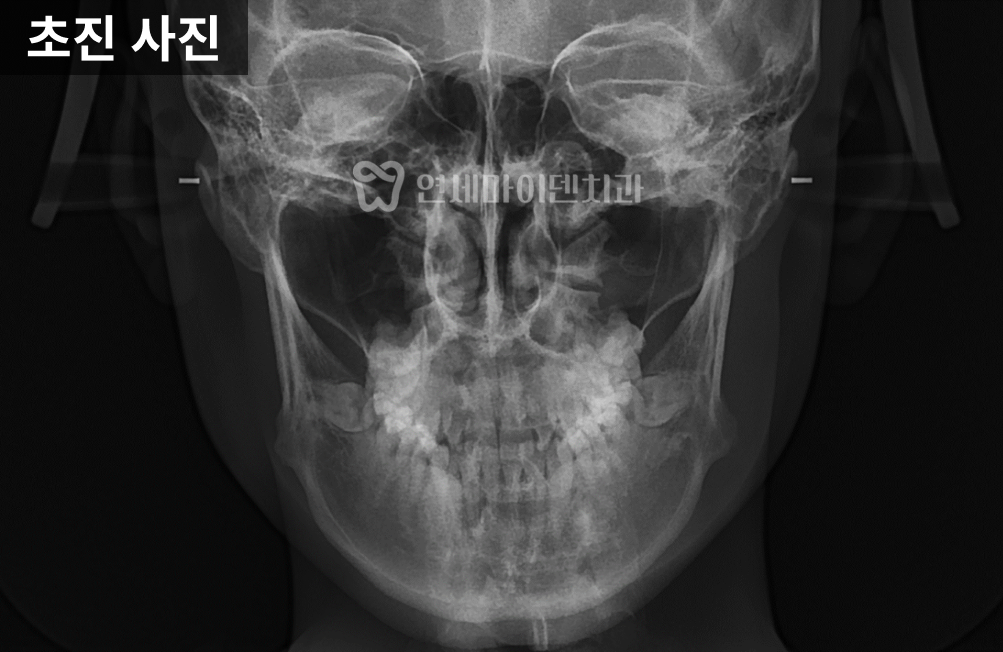

정면 방사선에서는

위턱과 아래턱의 폭 차이가 크게 나타났으며,

위턱이 약 10mm 이상 좁은 상태임을

확인할 수 있었습니다.